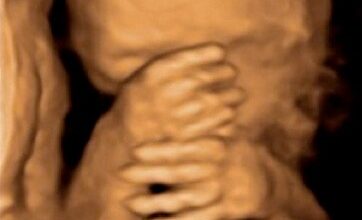

18/25

La evolución del feto a través de ecografías

Ecografía de 18 semanas: dos manitas con la ecografía en 3D.